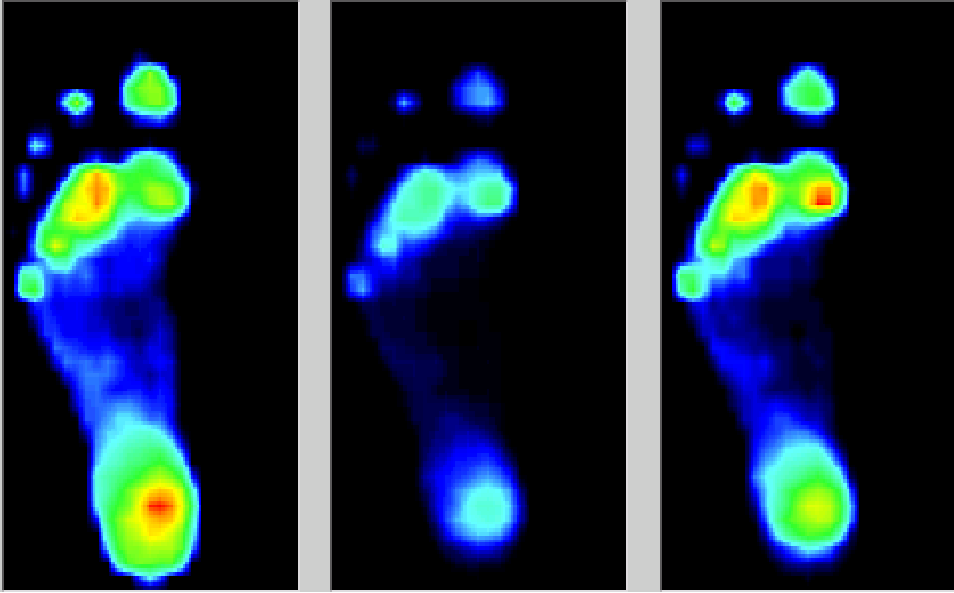

正常人的足底压力参数和分布有一定的规律,而当人处在疾病状态时足部畸形或功能异常可导致足底压力改变和分布异常。糖尿病状态下,不但足底压力会升高,且足底压力分布不均衡。

med压力怎么弄如何通过足底压力分布测试系统发现早期糖尿病足?_https://www.jmylbn.com_新闻资讯_第3张

注:红色彩区域域为高压区

前足和跖骨头部位局部压力升高,且前足/后足压力比升高;内外因素共同影响,使得糖足患者更容易出现损伤。